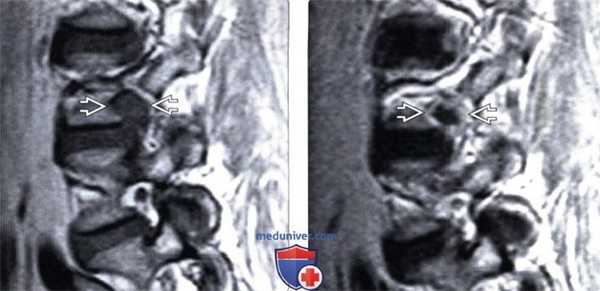

(Слева) Т1-ВИ, сагиттальный срез: крупная экструзия диска L4-L5, полностью заполняющая собой межпозвонковое отверстие и перекрывающая периневральную клетчатку Расположенный в отверстии корешок L4 идентифицировать как отдельное анатомическое образование здесь невозможно.

(Справа) Т1-ВИ с КУ, сагиттальная проекция: фораминальная грыжа диска L4-L5, характеризующаяся четким периферическим усилением сигнала.